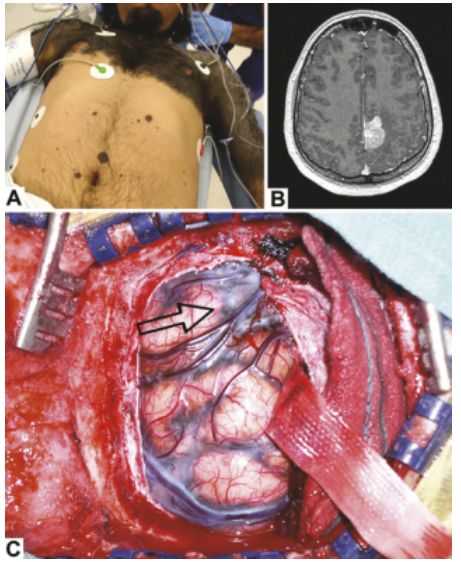

6.多毛症合并颅内黑色素瘤1例报道

Hypertrichosis lanuginosa acquisita associated with intracranial melanoma: case illustration.

PMID: 28707995 DOI: 10.3171/2017.2.JNS162723.

本文首次在文献中报道1例多毛症(Hypertrichosis lanuginosa acquisita, HTLA)合并颅内黑色素瘤病例,临床表现、影像图片、术中所见如下图所示。

【周川】